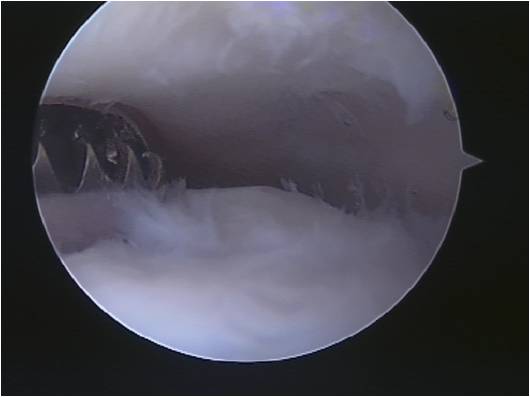

Keyhole(arthroscopic) surgery (Fig 3) may be helpful to remove scar or inflamed tissue (synovitis), spurs and loose bodies and deal with localized damage to the ankle joint surface. Such cartilage reconstructive techniques include drilling of cartilage supporting bone (micro-fracture) or cartilage grafting from elsewhere in the ankle or the knee.